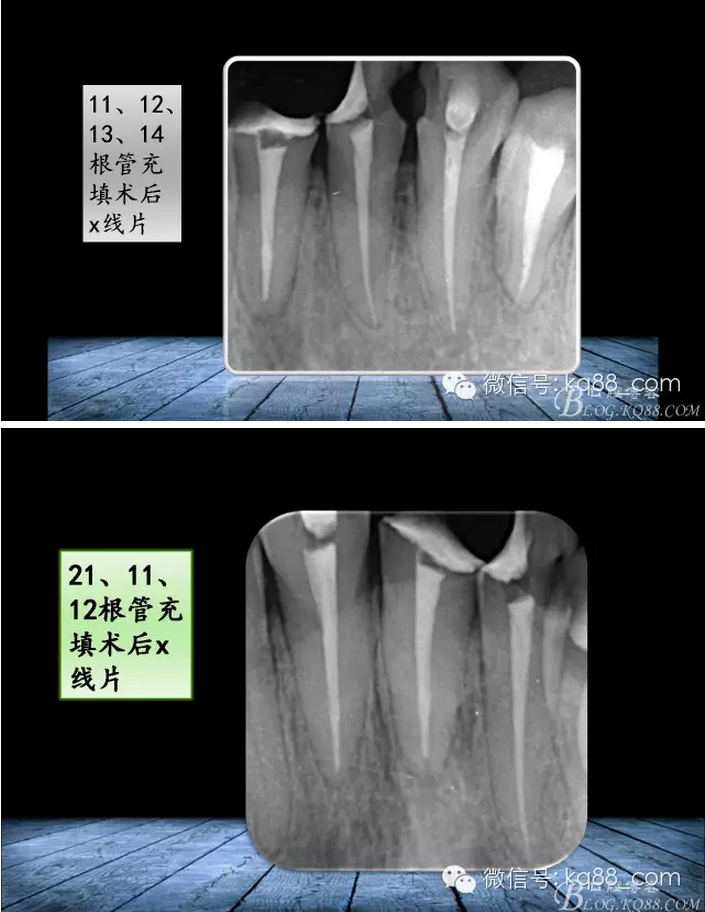

QQ圖片20150817140633.png

QQ圖片20150817140707.png